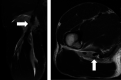

Methods: Two board-certified orthopaedic surgeons, highly experienced in reviewing MRIs, independently and retrospectively reviewed all MRIs collected at the Tokyo 2020 Olympic Games from clinical reports generated by board-certified musculoskeletal radiologists at the IOC Polyclinic. The presence and anatomical site of muscle injuries were classified as: type a: myofascial/peripheral; type b: muscle belly or musculotendinous junction; and type c: injury which extends into the tendon, with reference to the British Athletics Muscle Injury Classification.

Results: Fifty-nine MRI-detected muscle injuries were seen in 40 male and 19 female athletes. 24 athletes (41%) were unable to fully compete in their event. Fifty-two injuries (88%) involved lower extremity muscles with hamstring muscle injuries most common (32 of 59, 54%). Half of all muscle injuries occurred in athletes participating in athletics (30 of 59, 51%). 21 athletes (35%) sustained type a injuries, 14 athletes (24%) type b injuries and 24 athletes (41%) type c injuries. Of athletes with type c injuries, 18 (75%) did not complete their competition, a rate significantly higher than types a and b (OR 14.50, 95% CI 4.0 to 51.9, p<0.001).